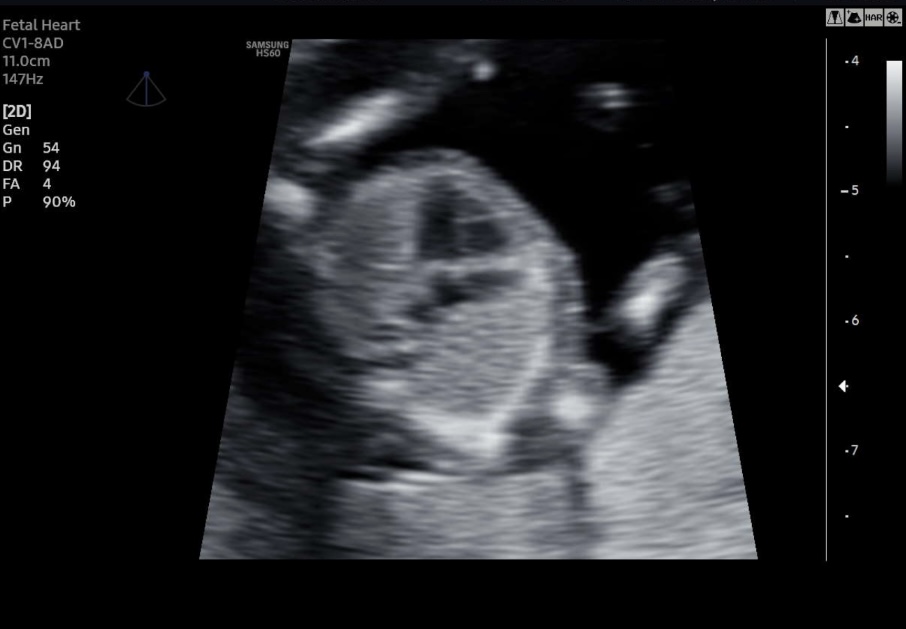

I have found more pictures that are maybe useful. Unfortunately no clear picture from the side with a nub what makes me think boy. Please help me with your guesses:-)Attachment 43795Attachment 43796Attachment 43797Attachment 43798Attachment 43799Attachment 43800Attachment 43801Attachment 43802

Also found this image of a possible potty shot. Any boy or girl parts visible over here?

There is no nub visible on any of these. I just can't guess based on any of these photos.